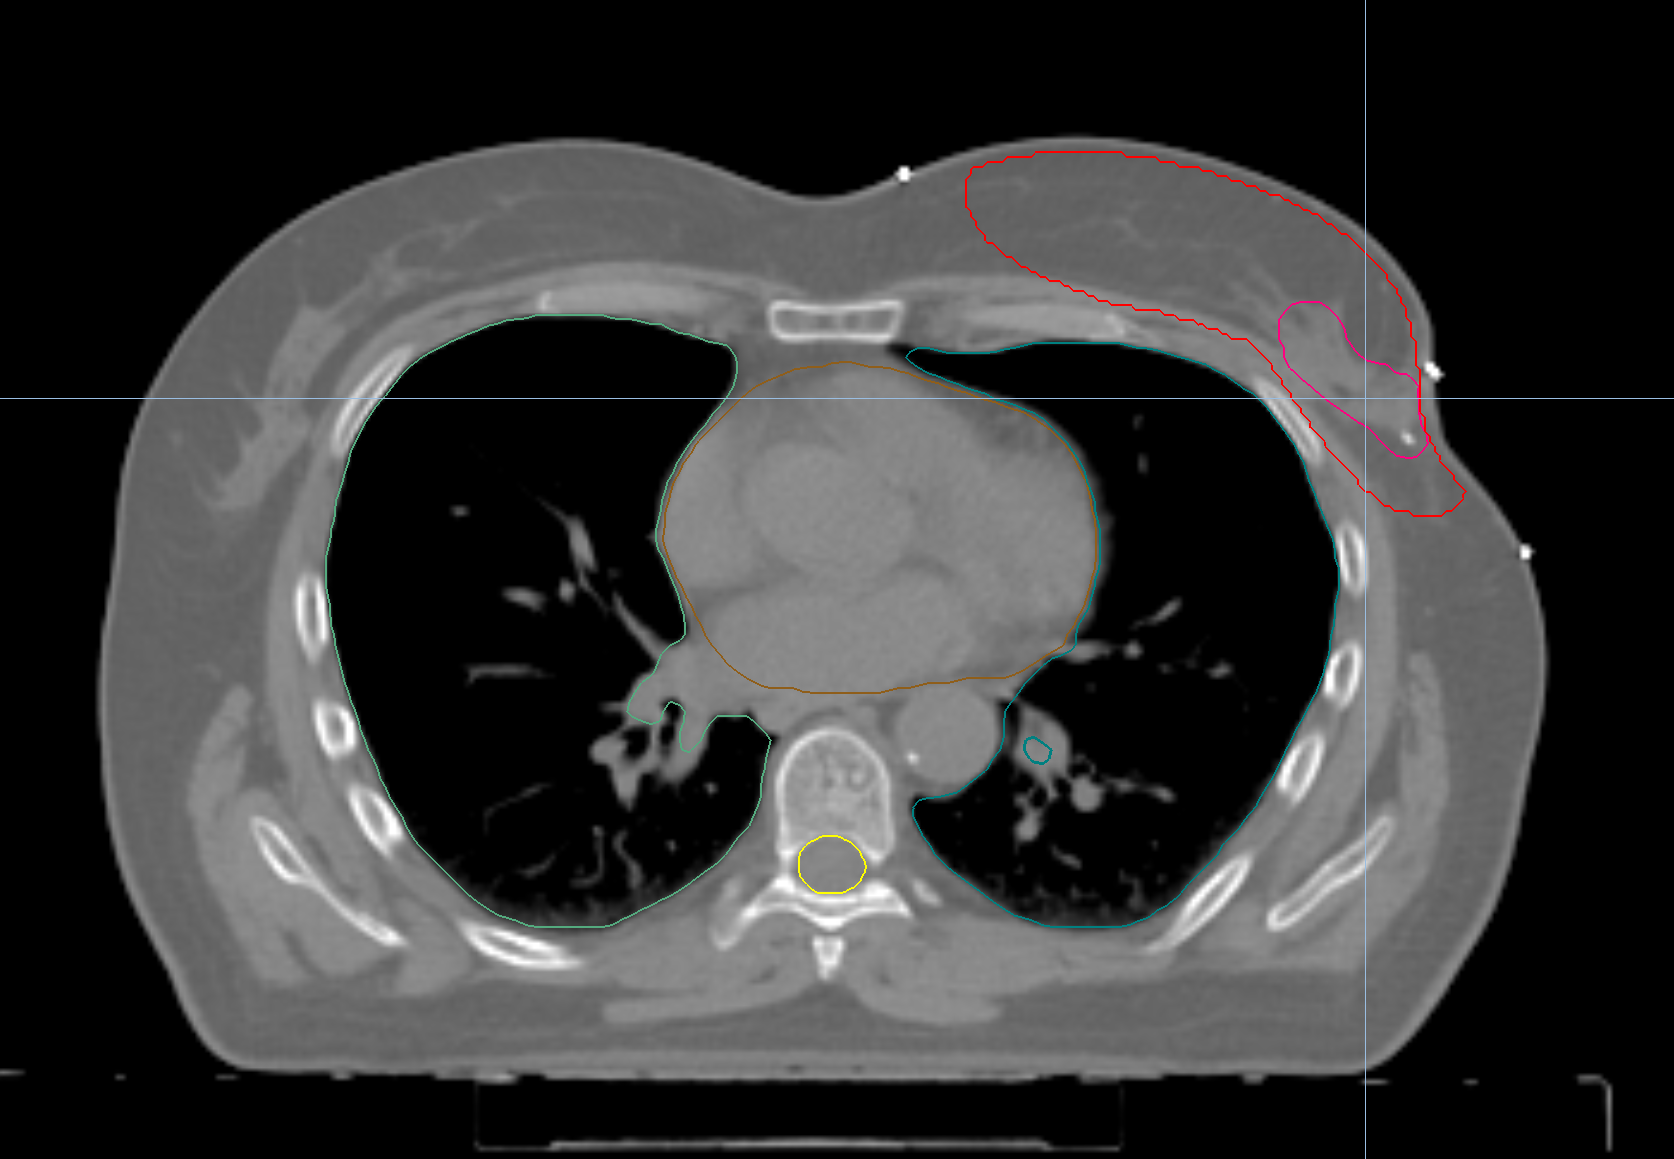

Left Breast with Deep Inspiration Breath Hold

< View All Plan Studies RADIXACT SYSTEM Left Breast with Deep Inspiration Breath Hold Case History AGE: 76-year-oldGENDER: Male Medical History Immidiate tolerance: Grade II dermatitis with eyelid edema, Grade I conjunctivitis resolved with Sterdex Diagnosis: Squamous cell carcinoma of the right lower eyelid Planning CT Images Treatment Plan Images